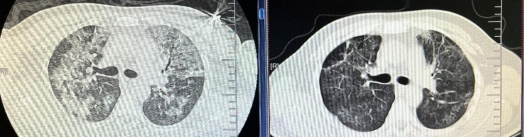

患者为47岁男性,醉酒后外伤导致下颌骨体部断裂、上颌骨牙槽骨折、鼻骨舌骨骨折,因误吸导致心跳呼吸骤停,北京口腔医院立即行心肺复苏、紧急气管切开、呼吸机辅助通气、血管活性药物泵入维持血压,3分钟后恢复自主循环。口腔医院第一时间启动院际转诊机制,转入我院呼吸与危重症监护室时双肺均呈"白肺"表现,血气分析提示严重呼吸衰竭,氧合指数PaO2/FiO2<100(氧合指数为肺脏将吸入的氧气转化为动脉血中氧气的能力,正常值为400-500mmHg),呼吸团队迅速完善支气管肺泡灌洗,病原学结果提示多重耐药菌肺炎(金黄色葡萄球菌+屎肠球菌+肺炎克雷伯菌),予美罗培南+万古霉素精准抗感染、有创呼吸机辅助通气维持氧合。经积极治疗后,患者痰量减少,炎症指标显著下降,但仍高热,血氧饱和度改善不明显,复查胸CT考虑

感染后机化,在病程第8天果断加用甲强尼龙进行免疫调节,逆转肺纤维化进程。历经13天治疗,患者肺部病灶显著吸收(CT复查渗出减少80%),成功撤离呼吸机并封堵气切套管,最终安全转回北京口腔医院完成颌骨重建手术,恢复良好。